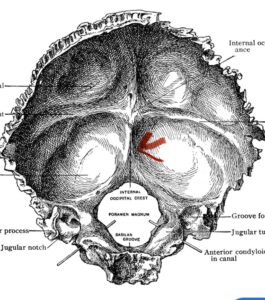

Although some patients do not require a decompression and just require an occipital cervical fusion, most require some sort of decompression of the neural elements. After a decompression an instrumented fusion is performed. A useful anatomic structure for anchoring the top portion of the construct to the skull is the midline keel of the subocciput. This structure extends from the external occipital protuberance, which corresponds to the confluence of the sagittal and transverse sinuses, to just above the foramen magnum:

(Fig. 1). This bone is quite thick, about 15 mm (Figs. 2a and b). Most modern plate systems utilize three midline keel screws with the option to place within a 2 cm lateral fixation point. This plate is connected to sometimes tricky-to-bend rods and connected to screw fixation points in the cervical spine (Fig. 3). Bone graft material extends from skull to cervical spine.

Fig. 1: Diagram of occipital bone to foramen magnum. Note external occipital protuberance (red arrow)

Fig. 2a: Cartoon illustrating posterior projection of internal skull structures demonstrating the midline keel in the subocciput above the foramen magnum.